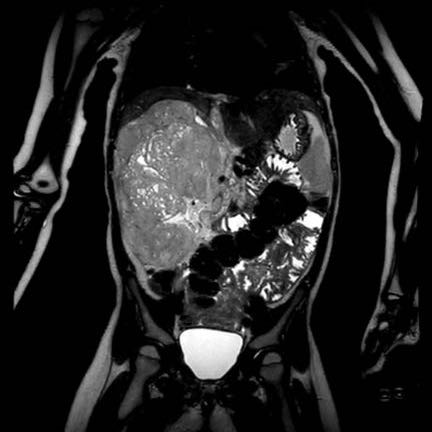

Ca lâm sàng 1

Hình ảnh chuỗi xung T2W mặt phẳng coronal cho thấy một khối u không đồng nhất ở thận trái với các thành phần nang nhỏ.

Khối u ngấm thuốc kém hơn so với phần nhu mô thận bình thường còn lại ở ngoại vi.

Các thành phần đặc của khối u cho thấy hạn chế khuếch tán rõ rệt (mũi tên).

Đây là u Wilms ở bé trai năm tuổi. Hóa trị tiền phẫu được thực hiện theo phác đồ Umbrella của SIOP-RTSG, sau đó tiến hành cắt thận.